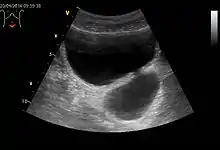

Діагностика

- Комп'ютерна томографія. Дозволяє оцінити стан кишечника, констатувати наявність дивертикулу, потовщення кишкової стінки, периколітичний абсцес, фістули тощо.